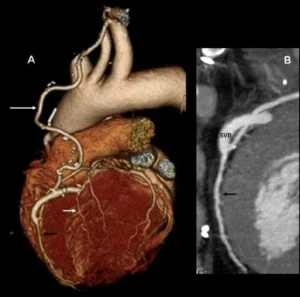

КТ-коронарография является высокоинформативным методом диагностики, позволяющим оценить состояние сердца и коронарных артерий. Исследование проводится с использованием мультиспирального компьютерного томографа с контрастированием сосудов.

Во время процедуры пациенту вводится контрастное вещество, благодаря которому становится возможной точная визуализация сосудов сердца и выявление потенциальных сужений или блокировок кровотока.

- возможность получения трёхмерных изображений коронарных артерий.